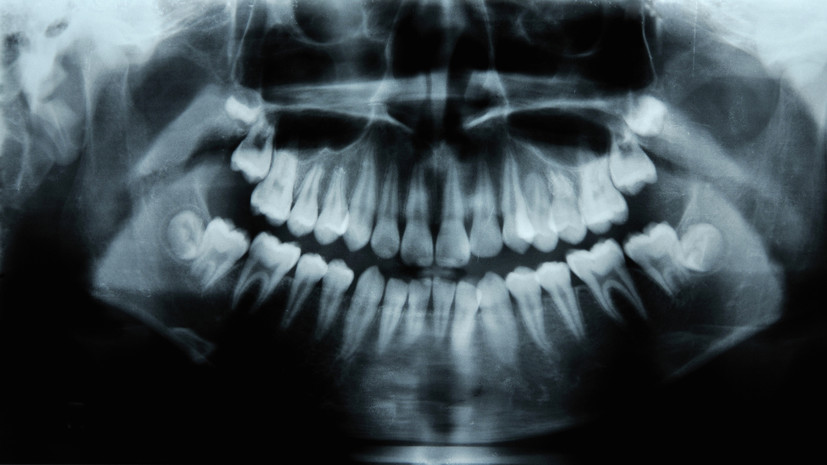

- Gettyimages.ru